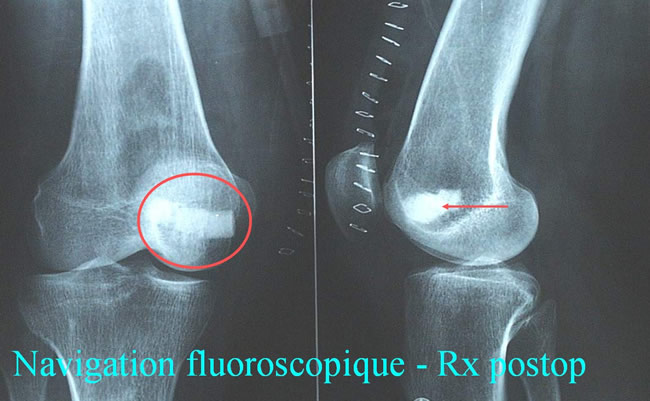

Navigation fluoroscopique : Radios standard

Femme agée de 48 ans : douleur du genou, impotence fonctionnelle, limitation d'amplitudes articulaires.

Radios des genoux face et profil - zone de condensation sur la face axiale du condyle médial du fémur droit.

Navigation fluoroscopique - Rx postop.

L'intérêt de la chirurgie assistée par ordinateur dans l'excision de l'Ostéome Ostéoïde. Navigation scannographique et fluoroscopique: 2 cas cliniques A.Eid MD; A.Badulescu MD; T.Martinez MD; P.Girard MD; P.Merloz MD - AOLF 2002